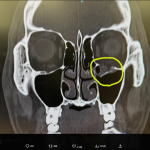

左目が下がり、複視が起きるという@tonde_yamanより